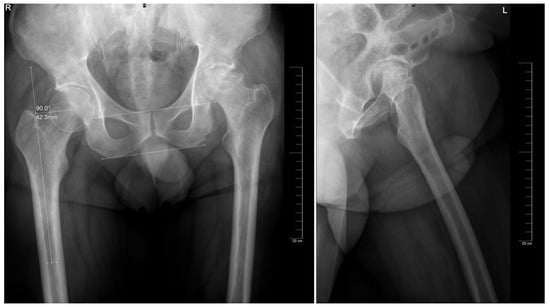

2.3. Digital Templating

The preoperative planning was performed manually in several phases. Starting with the anteroposterior view, the X-ray magnification is determined. Next, the landmarks are identified: the center of the femoral head, teardrop, anatomical axis of the non-target femur, and the ilioischial and transacetabular teardrop lines (Figure 1). The acetabular component size that fits the contour of the acetabulum was selected. The medial border is defined as the teardrop, and the cup is placed at 45 degrees of abduction. Afterward, the femoral component size that fits most precisely the contour of the canal is chosen, keeping in mind that it should be in contact with the lateral and medial cortex and must be in line with the anatomical axis of the femur. The upper part of the stem component must be located in the piriform fossa. The leg length discrepancy (LLD) is determined by the perpendicular distance from the middle of the lesser trochanter to the horizontal line drawn through the base of both teardrops, and the femoral medial offset (FMO) is calculated as the distance from the center of the femoral head perpendicular to the anatomical axis of the femur. The planning is performed on the lateral view using a similar approach (Figure 2). The acetabular template cup of appropriate size is placed with approximately 45 degrees of abduction. The medial border of the acetabular cup is positioned next to the ilioischial line and in close contact with the teardrop. The anatomical axis of the femur is marked, and the suitable femoral stem is chosen and positioned to fill the medullary canal. Postoperative radiographs are routinely performed to confirm proper positioning (Figure 3).

Figure 1. Identification of relevant landmarks and measurements of the hip and on the non-target side, on the anteroposterior and lateral view, respectively (bi-ischial line, interteardrop line, femoral offset).